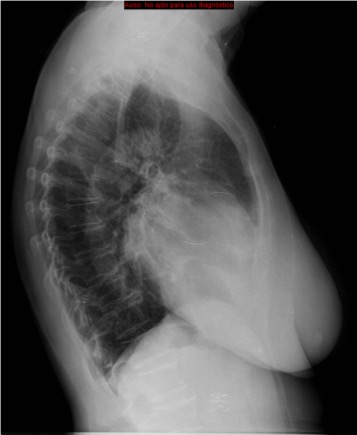

CASO: Febrícula y tos de 4 días de evolución.

Hallazgos:

- En la placa PA se observa una asimetría en los hilios pulmonares, el hilio izquierdo tiene una densidad aumentada.

- Tras examinar la placa lateral se observa un aumento de densidad en la columna que puede ser compatible con una condensación, es el signo de la desnificación vertebral.

SIGNO DE LA DENSIFICACIÓN VERTEBRAL: En la radiografía lateral normal, la densidad de la columna torácica tiende a disminuir desde la parte superior hasta el diafragma; la alteración de ese patrón por la presencia de una densidad superpuesta a la columna, indica la existencia de una consolidación pulmonar. Este signo adquiere especial valor cuando en la proyección posteroanterior la consolidación está oculta en el espacio retrocardíaco o en la base pulmonar.